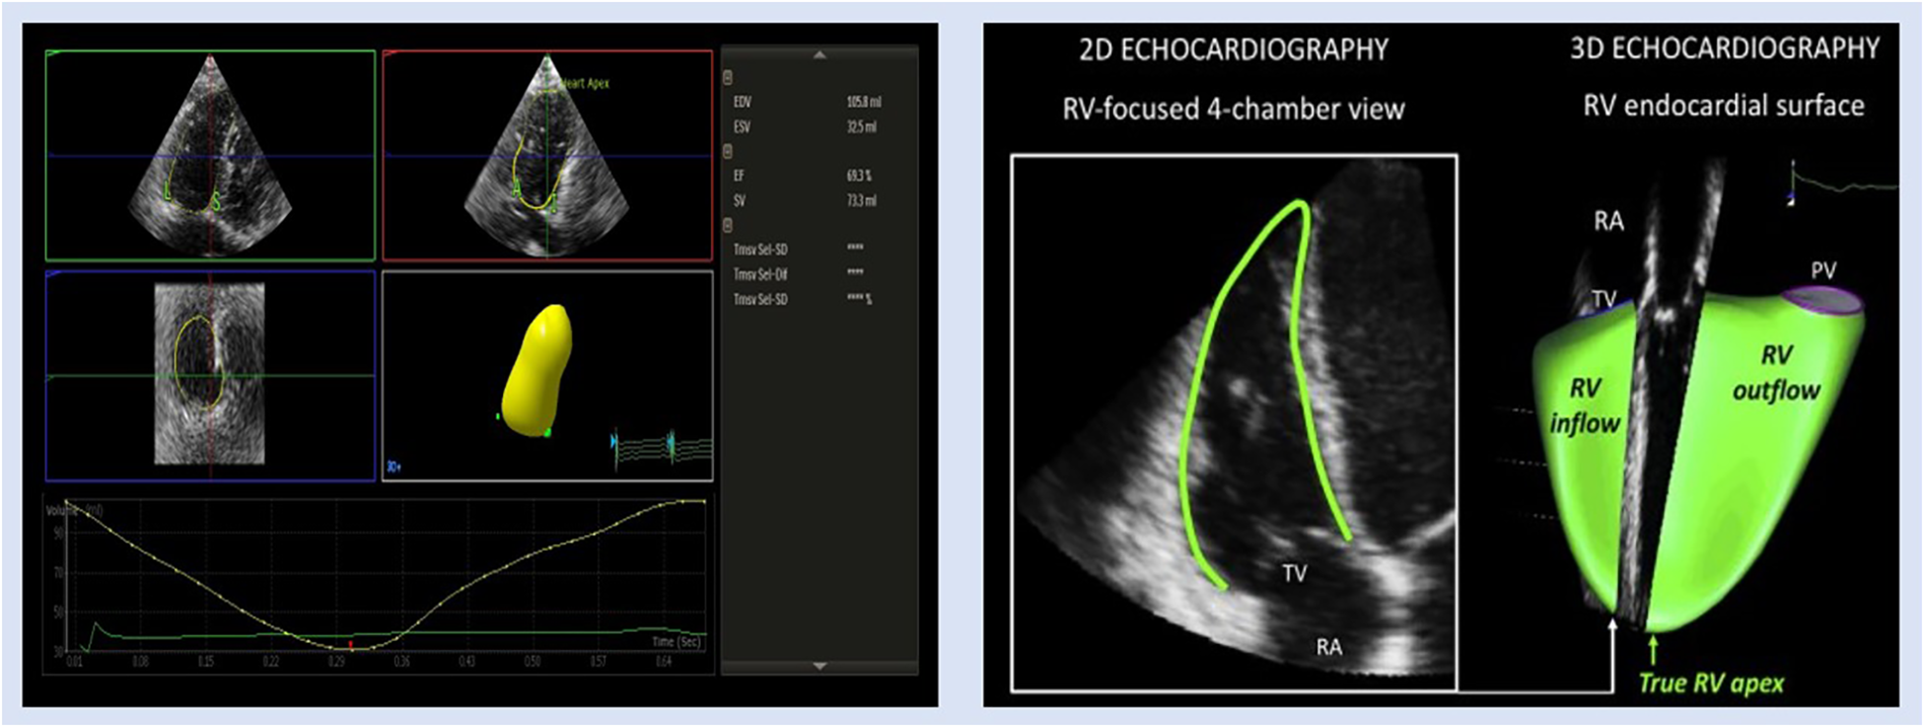

3D echocardiography

Owing to the complex geometry, crescent shape, and complex mode of contractility of the RV, 2D echocardiography (2DE) is unable to locate the RV inlet and outlet in the same image. Consequently, three-dimensional echocardiography (3DE) is a more precise and feasible tool than 2DE for the assessment of RV volumes and function (60). RV function measured with 3DE (Figure 3) was found to be more closely correlated with gold standards CMR and cardiac catheterization (36, 61–63). Despite this, the accessibility of 3D echo is greater than CMR, which makes this an attractive alternative. In addition, strain imaging has been combined with 3DE to accurately predict RV ejection fraction (EF) (64). A prior investigation by Vitarelli et al. (37) revealed a moderate association (Pearson correlation coefficient ranging from −0.51 to −0.64) between 3DE-RVEF and 3D-RVEF exhibited the highest area under the curve (0.89, P < 0.05) when compared with other 3DE parameters for hemodynamic indices found by RHC in identifying hemodynamic indicators of RV failure (a composite of Ci < 2 L/min/m2 and RA P > 15 mmHg). By receiver operating curve (ROC) analysis, 3DE-RVEF (0.89) has the highest area under the curve (AUC) (95% CI; 0.68–0.99, P < 0.05) with the cutoff value of EF 39% and 90% and 83% sensitivity and specificity, respectively. The most recent study by Liu et al. (63) demonstrated that 3DE-derived RVEF had the potential to predict the intermediate–high risk stratification (AUC 0.82, 95% CI 0.73–0.91, P < 0.001), which showed the best predictive capacity. To be specific, EF < 26.39% had an 81.6% sensibility and 73.8% specificity to predict intermediate–high risk stratification. 3D-RVEF (OR 0.82, 95% CI 0.75–0.90, P < 0.001) was identified as an independent predictor of intermediate–high risk stratification in patients with PAH. The authors concluded that 3DE-derived EF and free wall strain (FWS) had the potential to independently predict intermediate–high risk stratification in patients with PAH, and the predictive capacity was retained after adjustment for demographic data. Similar findings were found by Murata et al. (65), whose study's ROC analysis showed that 3DE-RVEF was more accurate in predicting cardiac events, such as hospitalization, intervention, and mortality than other hemodynamic measurements, such as mPAP, with an AUC of 0.78.

Figure 3

Representative images of 3DE RV assessment in patient with PH. EDV, end-diastolic volume; ESV, end-systolic volume; EF, ejection fraction; RA, right atrium; PV, pulmonic valve; SV, stroke volume; TV, tricuspid valve.

3DE-derived speckle tracking has proved itself a reliable method for RV systolic function evaluation and survival prediction (61, 64). Smith et al. (64) aimed to assess the RV strain with 97 consecutive patients with established pulmonary hypertension disease in comparison with 60 controls, with the help of 3DE-derived strain. In comparison with normal controls, the strain analyses (area strain, redial strain, circumferential strain, and longitudinal strain) were all found reduced. RV global area strain (RVGAS) was found to be a significant determinant of all-cause mortality [HR: 3.49; 1.21–7.07 with 95% confidence interval (CI); P = 0.017]. Hence, 3DE-derived strain analysis is a reliable tool for the assessment of disease outcome in such patients.